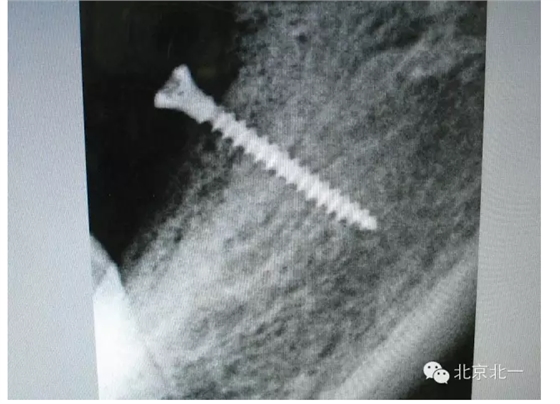

擅長(zhǎng):種植外科,尤其專長(zhǎng)復(fù)雜牙種植,自體骨移植同期種植,上頜竇底內(nèi)外提升同期種植技術(shù),美學(xué)區(qū)種植技術(shù),即刻種植外科與即刻負(fù)重技術(shù),軟組織成形外科種植技術(shù)及全口無牙頜ALL-ON-FOUR技術(shù),種植并發(fā)癥和種植急癥處置等手術(shù)治療,從事口腔頜面外科,正頜外科、頜面部整形、微創(chuàng)拔牙,笑氣無痛舒適種植十余年。